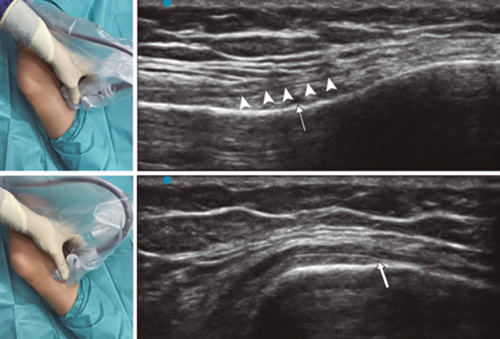

Para lograr una correcta ubicación de las referencias anatómicas por ultrasonido debemos colocar al paciente en posición supina con la rodilla flexionada y una almohada debajo de la fosa poplítea (14,16,19). Después de realizar asepsia/antisepsia de la rodilla, colocación de campos quirúrgicos y de la funda estéril del transductor lineal de alta frecuencia, procedemos a ubicar el NGSM (Figura 3). Colocando la sonda en un plano coronal sobre la cara interna de la rodilla, la deslizamos en sentido craneal hasta visualizar la unión de la metáfisis con la diáfisis femoral y la arteria/nervio geniculado superomedial (ANGSM), usualmente están localizados cerca al periostio del fémur (en caso de no encontrar esta estructura neurovascular, se toma como referencia la unión de la metáfisis y la diáfisis femoral). Después se marca en la piel el punto medio del transductor que corresponde a la ANGSM y se gira el transductor para ubicarlo en el plano transversal o axial para visualizar la ANGSM en eje corto (si no es posible la visualización de esta estructura, confirmar que estamos a un 50 % de la profundidad del fémur). En este corte transversal se avanza la aguja de RFT en plano desde anterior a posterior hacia la ANGSM o hasta una profundidad del 50 % del espesor del fémur. Finalmente se vuelve a girar el transductor 90°, dejándolo en un plano coronal para comprobar que la punta de la aguja está cerca de la ANGSM o de la unión de la metáfisis y la diáfisis femoral (14,16,19).

Fig. 3. Sonoanatomía y técnica para realizar el bloqueo del nervio geniculado superomedial (NGSM). El transductor se ubica en el eje largo distal del fémur y una vez que se tenga la posición del NGSM (asteriscos), se gira la sonda 90 grados para obtener una visión en eje corto del fémur (no olvidar mantener la misma profundidad a la que encontramos el NGSM en el eje largo). VM: vasto medial.

Para ubicar al NGIM (Figura 4) colocamos el transductor en un plano coronal sobre la cara interna de la rodilla, lo deslizamos en sentido caudal hasta identificar la unión de diáfisis con la metáfisis tibial y la arteria/nervio geniculado inferomedial (ANGIM), y repetimos los mismos pasos que usamos para el NGSM. En caso de no encontrar la ANGIM, la referencia que se tomará será la profundidad del 50 % del espesor de la tibia (14,16,19).

Fig. 4. Sonoanatomía y técnica para realizar el bloqueo del nervio geniculado inferomedial (NGIM). El transductor se ubica en el eje largo proximal de la tibia e identificamos el paquete vasculonervioso del NGIM (flecha) justo debajo ligamento colateral medial (puntas de flechas). Luego se gira la sonda 90 grados para obtener una visión en eje corto de la tibia (no olvidar mantener la misma profundidad a la que encontramos el NGIM en el eje largo).

Para ubicar el NGSL, el paciente debe estar en posición supina con el miembro inferior en rotación interna, consiguiendo una buena exposición de la cara lateral del muslo. Colocamos el transductor lineal en un plano coronal sobre la cara lateral de la rodilla, lo deslizamos en sentido craneal hasta visualizar la unión de la metáfisis con la diáfisis femoral y la arteria/nervio geniculado superolateral (ANGSL), y repetiremos los mismos pasos que usamos para el NGSM (14,16,19).

Después comprobamos que el umbral de estímulo sensitivo a 50 Hz que desencadene una parestesia o dolor sea menor de 0,6 V, y para evitar daño de nervios motores no debe existir fasciculaciones del miembro inferior con un estímulo motor a 2 Hz con 2,0 V. Si todo está correcto, administramos 2 ml de lidocaína al 2 % o mepivacaína al 2 % en cada nervio y procedemos a realizar la RFT a 80 °C durante 90 segundos (9,14).